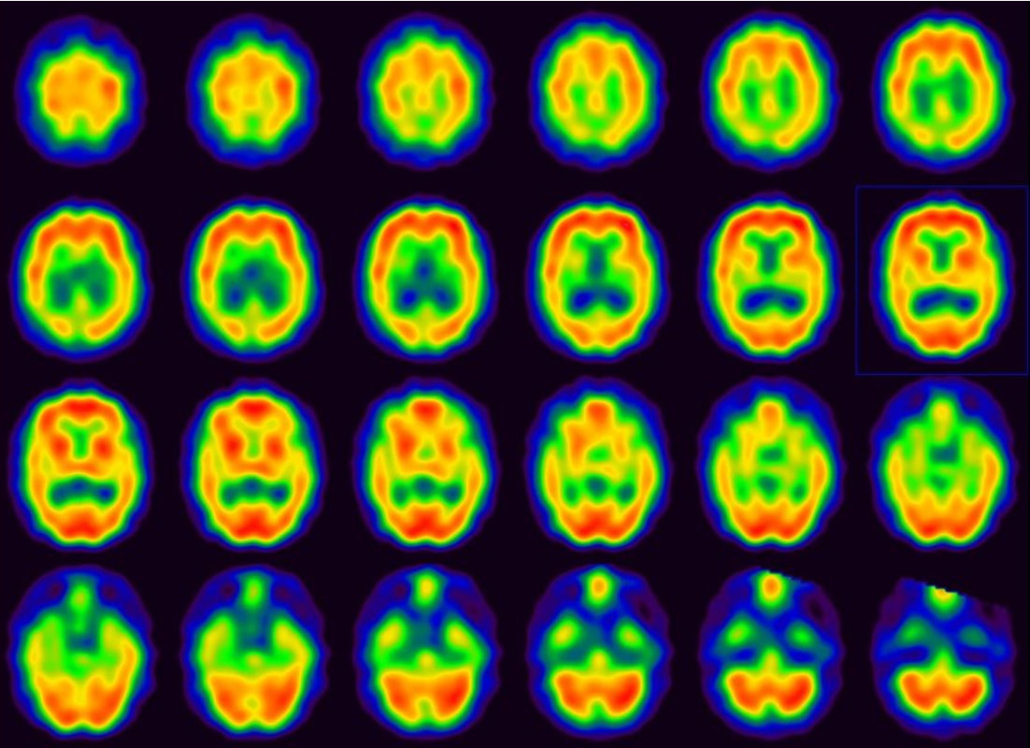

El número de “demencias” es elevado. La más conocida y frecuente es la enfermedad de Alzheimer (antigua “demencia senil”), que suele comenzar con fallos en la memoria reciente, y que afecta sobre todo a las personas de mayor edad, pero que puede presentarse en edades tempranas, incluso por debajo de los 50 años. La segunda en frecuencia es la “demencia vascular”, que se debe a lesiones vasculares en el cerebro (infartos o hemorragias) y puede afectar a diferentes facultades según dónde se produzcan estas lesiones, por lo que prevenir su aparición o progresión es primordial para una adecuada salud cognitiva. Otros tipos de “demencia”, como la “demencia fronto-temporal”, afectan más a la conducta y comportamiento de los pacientes, generando dificultades para la convivencia familiar y social. En todos estos casos, lo más importante es detectar el problema lo antes posible, para alcanzar un diagnóstico temprano y aplicar las medidas preventivas y terapéuticas existentes para su control o, cuanto menos, enlentecer el curso natural de la enfermedad, según su causa.

La mayor parte de estos problemas no disponen de un test diagnóstico directo, es decir, de una prueba en clave de “positivo o negativo” que permita confirmar o excluir con ella de forma absoluta que se padece la enfermedad. Sólo la evaluación directa por un neurólogo, en muchos casos apoyado también por la evaluación de un neuropsicólogo, y por la interpretación de las pruebas complementarias oportunas, nos permite alcanzar un diagnóstico de probabilidad fiable con el que tomar las medidas oportunas en pro de mejorar en lo posible su pronóstico.